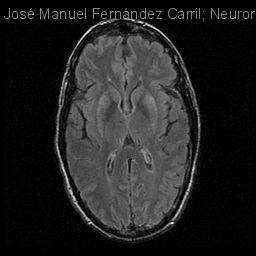

Encefalopatía postanóxica retardada.

Hombre | 51 años

Diagnóstico final: Encefalopatía postanóxica retardada

Neurología: Patología cerebrovascular

José Manuel Fernández Carril - Hospital Universitario De Guadalajara